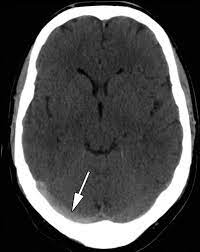

Cerebral venous sinus density on noncontrast ct correlates with hematocrit. Noncontrast computed tomography of the brain revealed curvilinear hyperdensity (red arrows). Aha scientific statements ⅲ venous thrombosis ⅲ sinus thrombosis, intracranial ⅲ brain infarction figure 1. See that article for a discussion of that specific clinical entity. Cerebral venous sinus thrombosis in children:

Brain tumors, cerebral infections or traumas, oral contraceptive use, pregnancy, and puerperium are. Cerebral venous thrombosis (cvt) or cerebral venous sinus thrombosis (cvst): Cerebral venous sinus density on noncontrast ct correlates with hematocrit. Cerebral venous thrombosis (cvt) is an uncommon disorder in the general population. Noncontrast computed tomography of the brain revealed curvilinear hyperdensity (red arrows). Cerebral venous and sinus thrombosis (cvst) is a rare disease responsible for less than 1% from the total of avc causes (bajenaru, 2010). The venous circulation of the brain is done. A statement for healthcare professionals from the american heart association/american stroke association.